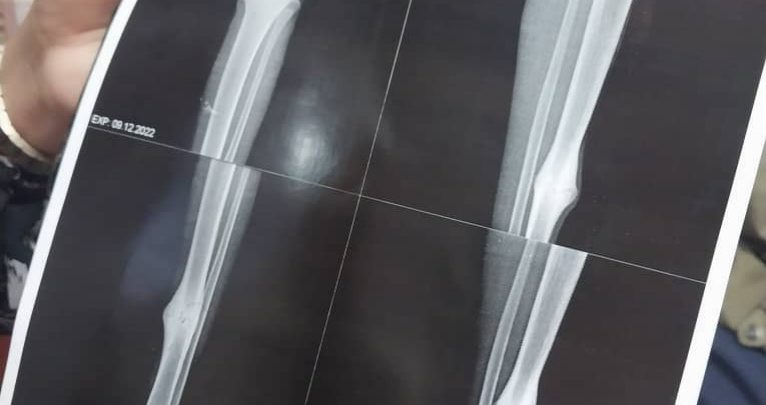

على خلفية مناشدة الطبيبة مزن الهادي بشرى، قيادات الدول والخيرين في السودان علاج طفل يجلس جوار إحدى البقالات بالخرطوم، استجاب المدير العام لجهاز المخابرات العامة الفريق أول أحمد إبراهيم مفضل، للنداء وتكفل بدفع تكلفة كل فحوصات وعلاجات الطفل وكل متطلبات العلاج بمستشفى الأمل.

وكانت الطبيبة قد ذكرت عبر لايف على صفحة والدتها الأستاذة منال مبارك، على فيسبوك، أنها وأثناء مرورها بجوار بقالة سندس طلب منها الطفل مساعدة، فقدمت له مبلغا من المال لكنه رفض المبلغ وطلب منها المساعدة في إجراء عملية لرجله المكسورة، ويحتاج (حذاءا) فسارعت الدكتورة بنشر لايف عبر مواقع التواصل الاجتماعي وناشدت عبره كل الخيرين دعم الطفل.

وكان مدير الجهاز أول المبادرين، حيث أجريت له كل الفحوصات اللازمة والبدء في العلاج فورا عصر اليوم.